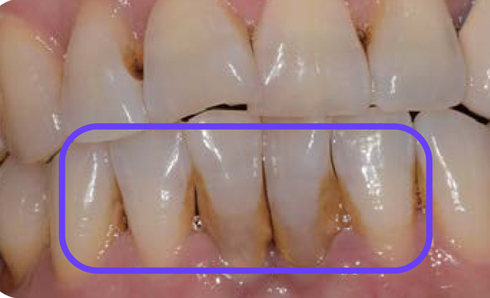

전

후

치석과 염증이 제거되며 스켈링 전보다 다소 잇몸이 내려가고 치간이 넓어진 느낌에 놀라실 수도 있습니다. 하지만 이는 치석과 염증이 있던 공간이 비워지고 잇몸이 원래의 잇몸뼈 부근으로 자리를 잡으며 생기는 변화입니다.

치석과 염증 등으로 잇몸과 잇몸뼈의 공간이 4mm가량이나 벌어져있던 치료 전과 비교했을 때 치료 후에는 잇몸과 잇몸뼈의 공간이 2~3mm를 유지할 수 있게 됩니다.